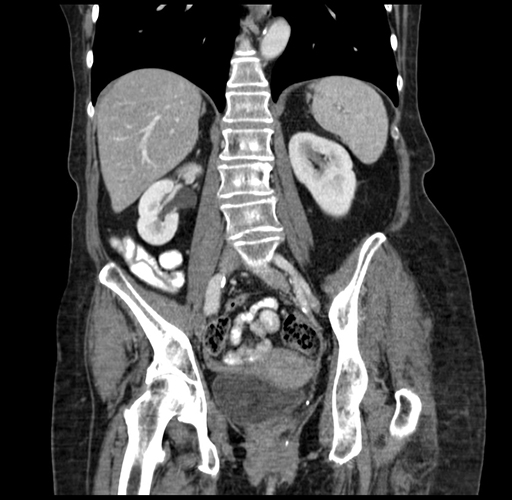

Pre-Chemo: Coronal Venous

Coronal Venous